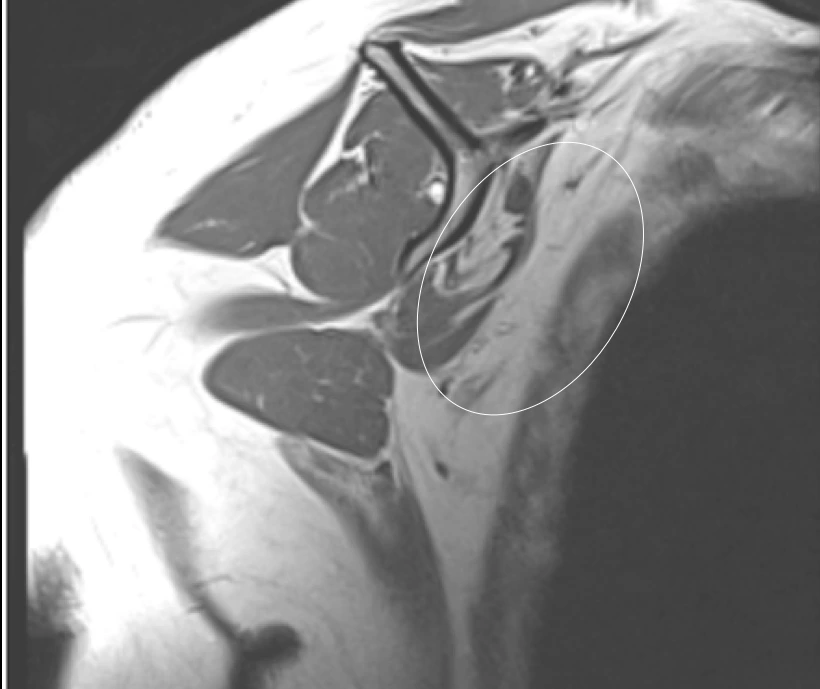

Errors in interpretation can send patients down the wrong treatment path.

Failure to describe the muscle atrophy accompanying this rotator cuff tear represents a missed chance to flag that the patient may be a poor candidate for surgery and unlikely to recover well.

Atrophied

Normal